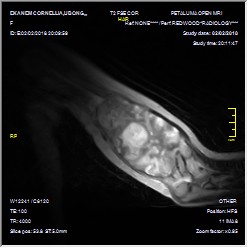

- Figure 3a_Axial MRI left arm

- Figure 3b. Coronal view MRI of the left arm